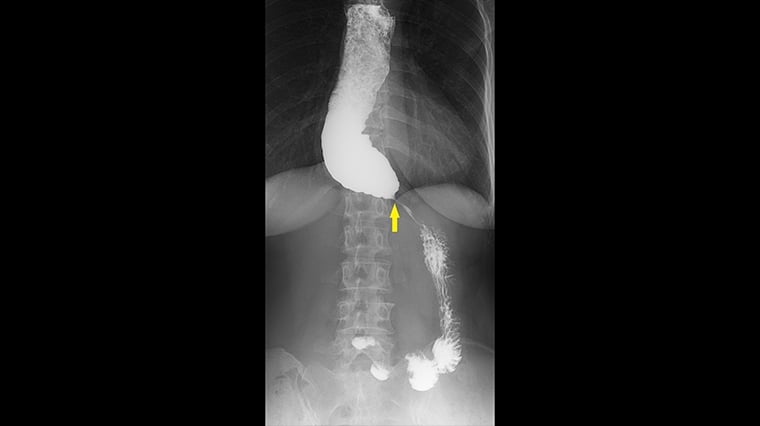

【NOW健康 楊芷晴/新北報導】60歲蕭女士多年來飽受進食後胸口悶脹、食物卡在胸口的不適所苦,症狀持續數年卻始終未能明確診斷。輾轉來到台北慈濟醫院後,首先接受食道攝影與食道高解析度壓力檢測(HRM),其中食道攝影顯示食道末端出現典型「鳥嘴狀」狹窄,但壓力檢測結果卻沒有典型下食道括約肌壓力上升表現,讓診斷一度陷入兩難。台北慈濟醫院胃腸肝膽科詹崴宇醫師接著以新式診斷工具功能性管腔成像探頭(Functional Lumen Imaging Probe, Endoflip)檢查,成功確診為「食道弛緩不能症」,讓蕭女士順利進行後續治療。

食道攝影及高解析度壓力檢測是臨床上食道弛緩不能症的標準檢查方式。詹崴宇醫師說明,食道攝影雖可觀察顯影劑流速及食道形狀,也能看到典型鳥嘴狀變化,即胃食道交界過緊而使食物過不去,造成上方的食道因為積壓而擴張,形成如同鳥嘴般的的狀態,但非黃金診斷標準;食道高解析度壓力檢測則是在病人清醒時做吞嚥測試,觀察食道蠕動波形,藉此觀察吞嚥時的壓力是否正常,雖是黃金診斷準則,但臨床上卻有部分病人的檢測結果不明確,導致無法確診,進行後續治療。